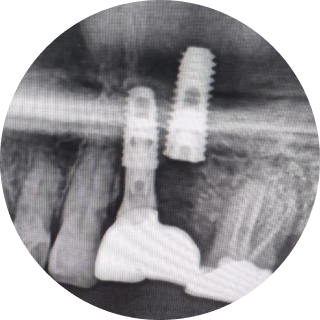

잘 못 심은 임플란트의 예시입니다.

이로운 치과는 디지털 진료를 통해 정확한 임플란트 식립 위치를 파악하여

아날로그 치료에서 발생할 수 있는 문제를 예방합니다.